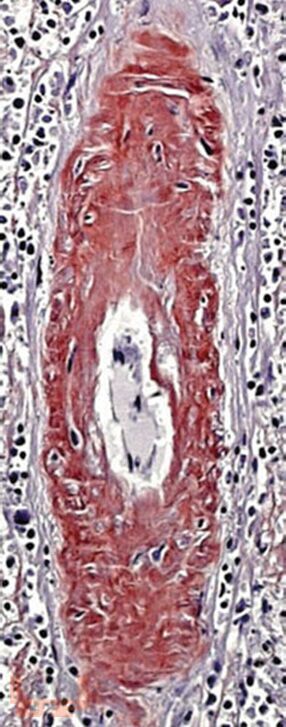

Учебное пособие посвящено клинико-морфологическим аспектам классификации и диагностики амилоидоза с использованием современных методов морфологии и иллюстративного материала. В пособии представлены краткий теоретический материал, ситуационные задачи с примерами решения и для самостоятельного выполнения, тестовые задания и ответы на них, что позволит студентам проводить диагностику амилоидоза с целью установления диагноза, способствует оценке морфофункциональных, физиологических состояний и патологических процессов в организме человека для решения профессиональных задач.